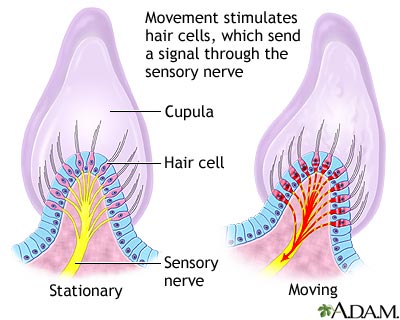

Vertigo is a feeling that you are spinning or moving, or that the world is spinning around you. Vertigo-associated disorders is a related topic.

Vertigo may be due to:

- Benign positional vertigo, a spinning feeling that occurs when you move your head

- Labyrinthitis, a viral infection of the inner ear that usually follows a cold or flu

- Meniere disease, a common inner ear problem that often also causes hearing loss or ringing in the ears (tinnitus)